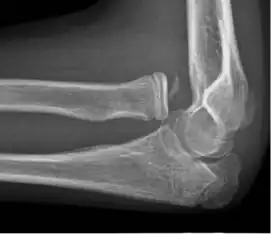

![X-ray of ventral dislocation of the radial head. There is calcification of annular ligament, which can be seen as early as 2 weeks after injury.[52]](./_assets_/X-ray_of_ventral_dislocation_of_the_radial_head_with_calcification_of_annular_ligament.jpg)